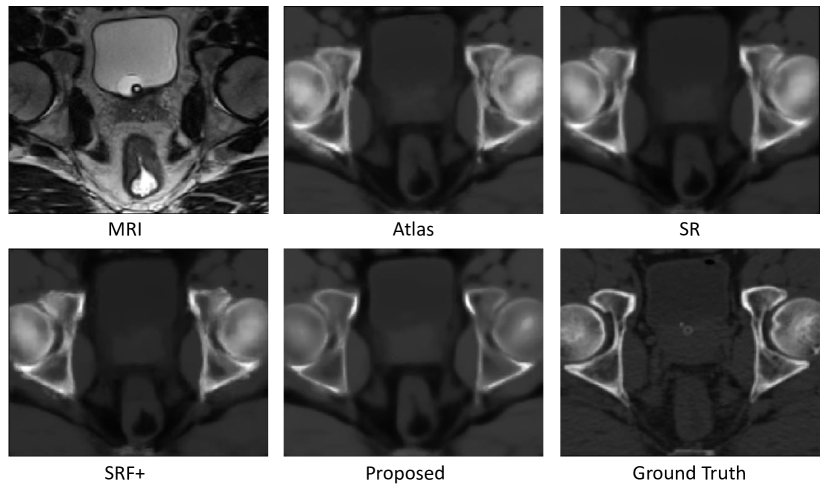

4.4 Experimental Results for Pelvic Dataset

The prediction results by the same methods used above but on the pelvic dataset are shown in Fig. 7. It can be clearly seen that our results are consistent with the ground-truth CT. The quantitative results based on the same metrics used in the previous dataset are shown in Table  2.

Refer to caption

Figure 7: Visual comparison of original MR images, the estimated CT images by our method and other methods, and the ground-truth CT images on 1 typical subject on the pelvic dataset

Quantitative results in Tables  2 show that our method outperforms the other methods in terms of both MAE and PSNR. Specifically, our method gives an average PSNR of 34.1, which is considerably higher than the 32.1 obtained by the state-of-the-art SRF+ method.